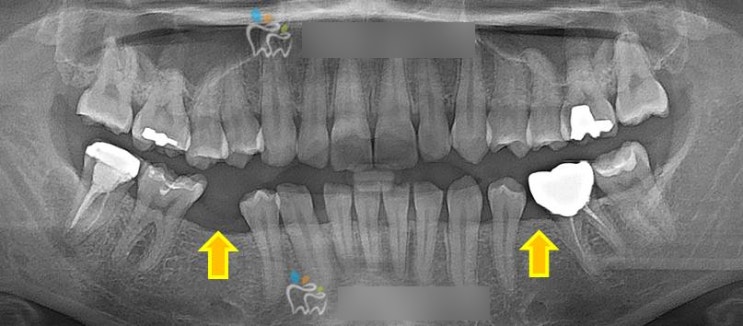

영구치(선천적 결손) 없는 과개교합 케이스 안녕하세요 교정전문의 최혜영 원장입니다. 오늘은 아래 작은어...